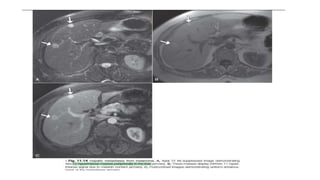

Imaging

• progressive enhancement in arterial, portal venous, and delayed

phases, thereby helping to distinguish it from HCC, which usually

has washout in the later 2 phases.

• Other associated findings may include hepatic capsular retraction,

vascular encasement that may lead to lobar atrophy, and dilatation

of peripheral bile ducts.

• MRCP: site of obstruction and extent of biliary tree involvement

• 5 yr survival <5%